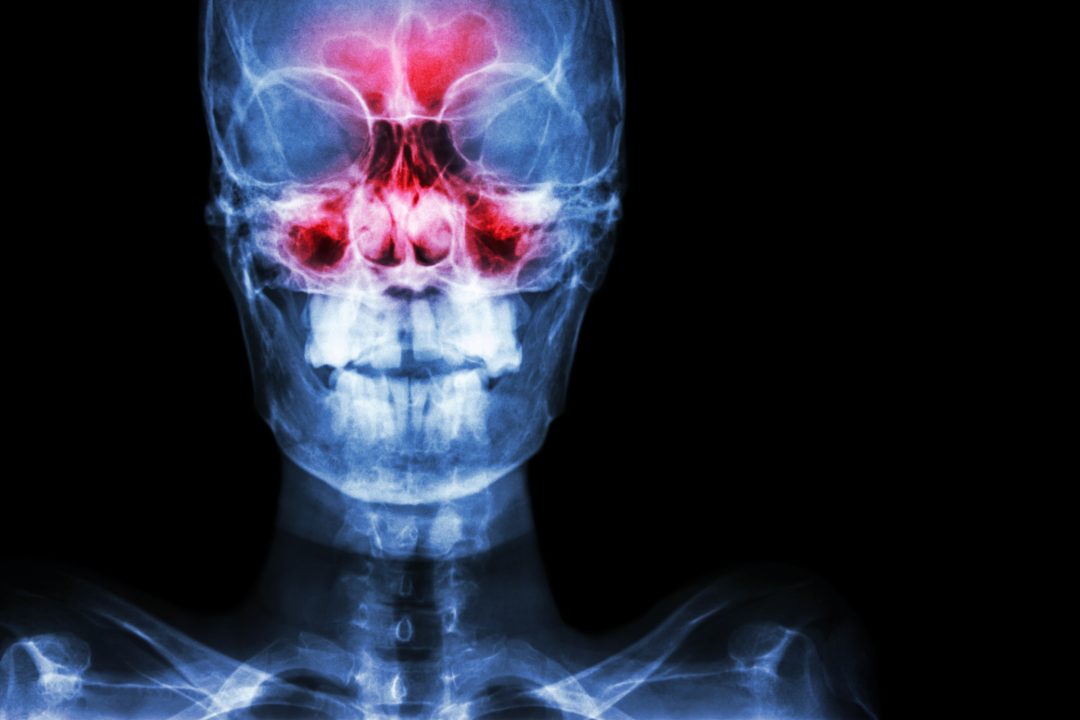

Chronic sinus inflammation alters brain activity

The millions of people who have chronic sinusitis deal not only with stuffy noses and headaches, they also commonly struggle to focus, and experience depression and other symptoms that implicate the brain’s involvement in their illness.

New research links sinus inflammation with alterations in brain activity, specifically with the neural networks that modulate cognition, introspection and response to external stimuli.